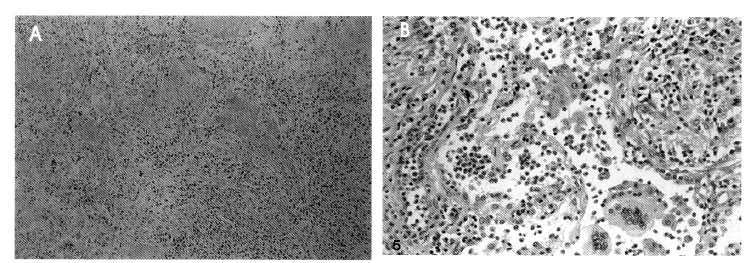

Figure 5.

Transbronchial lung biopsy specimen shows numerous eosinophils infiltrating the interstitium and alveolar space (A: H&E, ×100, B: ×400).